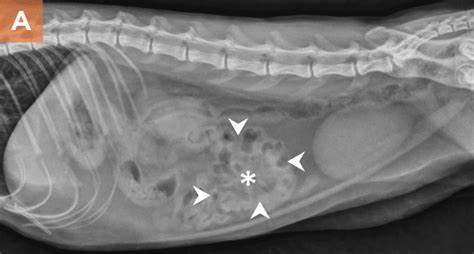

线状异物摄入后一般1-2天内出现反应,诊断也并不算困难,一般也不必非要钡餐显影

不可。线状异物会在肠道形成一串串葡萄,这是肠子被牵拉形成的,不难发现。如图:

图片